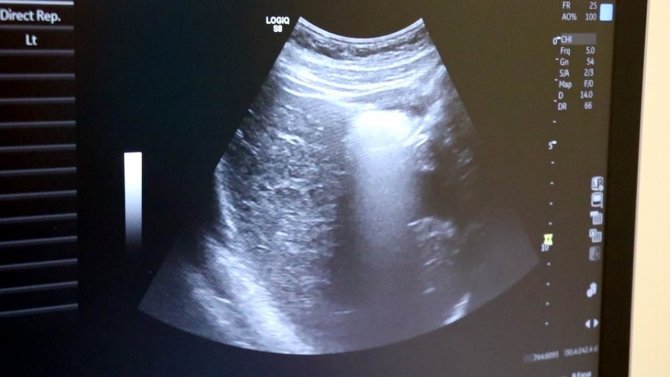

Ultrason uzun zamandan beri özellikle gebe annelerde sıklıkla başvurulan bir görüntüleme yöntemi. Yüksek ses frekanslarının işlenip ekrana yansıtılması ile elde edilen görüntülerle bebeğin sağlık durumunun yanı sıra birçok bilgiye de ultrason sayesinde erişmek mümkün olabiliyor. Medicana International Samsun Hastanesi Radyoloji Uzmanı Dr. İlker Eroğlu, 2 boyutlu ultrasonun ve 4 boyutlu ultrasonun hiçbir zararı olmadığını belirterek açıklamalarda bulundu.

Ayrıntılı ve 4 boyutlu ultrason ile bebeklerin doğmadan önceki sağlık durumlarının belirlenebileceğine değinen Uzm. Dr. İlker Eroğlu, "Ultrason; yüksek frekanslı ses dalgalarının bilgisayar işlemcisinde işlenip, kablo arayıcılığıyla monitöre aktarılmasıdır. Son yıllarda gebelikte ayrıntılı ultrason gerekliliği giderek artmaktadır. Yaklaşık 50 yıl önce ultrason yaygın değilken doğumlarda bebek nasıl doğacak, sağlıklı mı sağlıksız mı doğacak ya da cinsiyet bile bilinemiyordu. 4 boyutlu ultrasonda ya da ayrıntılı ultrasondan sonra bebeğin sakatlıkları doğumdan önce anlaşılıp, tedavisi mümkün olanlar da doğumdan önce tedavi edilebilir oldu. Böylelikle bebeklerin daha sağlıklı olarak dünyaya gelmesi sağlanmış oldu. O nedenle ayrıntılı ultrason gereklidir" dedi.

Renkli ultrasonlarda bebeklerin anne karnındayken sakatlığı olup olmadığının belirlendiğini ifade eden İlker Eroğlu, "4 boyutlu ultrason halk arasında "renkli ultrason" diye bilinir. Anneler bu ultrasonda bebeğin görüntüsünü anladığı için onu daha çok sever. Hekimler genelde ultrasona siyah-beyaz bakar. 4 boyutlu ultrason iç organlar hakkında detaylı bilgi vermez. Biz detaylı ultrasonda (2. düzey ultrason) bebeğin iç organlarına yönelik incelemeyi siyah beyaz olarak yaparız. O nedenle bizim için siyah-beyaz ve 2 boyutlu olarak yapılan inceleme daha önemlidir. 4 boyutlu ultrasonda da faydalandığımız yerler vardır. 4 boyutlu ultrasonda örneğin; bebeğin kolu-bacağı yoksa, dudak yarığı varsa, gösterebiliriz. Çeşitli anatomik deformasyonları da anneye gösterebiliriz. Hala dünyada ayrıntılı ultrason 2 boyutlu ve siyah-beyaz olarak yapılır" diye konuştu.

Uzun yıllardır ultrasonun kullanıldığını ve bir zararının saptanmadığını belirten Dr. Eroğlu, "Ultrason dünyada çok uzun yıllardır kullanılan bir görüntüleme yöntemi. Bizim kulağımızın duyamayacağı yüksek frekans ses dalgaları ile çalışır. Uzun yıllardır kullanılan ultrasonun hiçbir zararının olmadığı görülmüştür. Hastalarımız gönül rahatlığıyla ultrason yaptırabilir. Detaylı ultrason, 2. düzey ultrason, 4 boyutlu ultrason; bunların hepsi aynı işlem. Normalde dünyada 18-22'inci haftalar arasında yapılır ancak klinik tecrübemiz gereği 21 ya da 22. haftada bakmayı tercih ederiz" şeklinde konuştu.